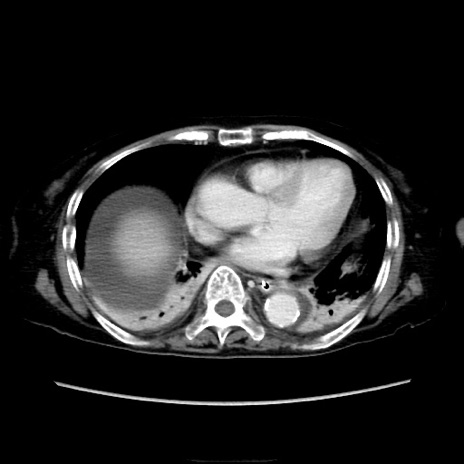

症例40(横断像)

他院CT

横断像